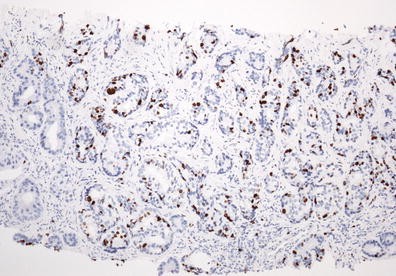

CRABP I expression in the cell cytoplasm of pNET G2 (Ki-67–9 %).:

figure b